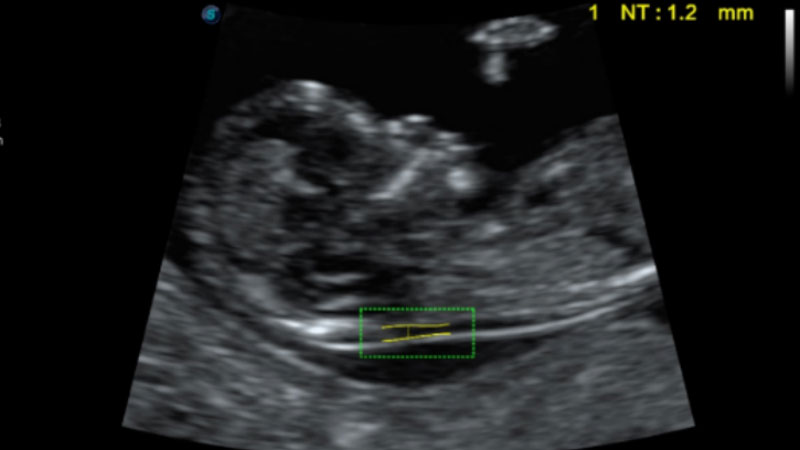

S-Fetus基于大數據深度學習算法,能夠幫助您在產前篩查過程中智能識別胎兒標準切面、自動測量并錄入報告。一個按鍵,即可智能、精準、高效地獲取胎兒生理指標,極大簡化您的產科檢查操作。

自動識別頸項透明層并獲得NT值,為早孕胎兒畸形篩查提供有效測量工具,提高診斷效率和診斷信心。